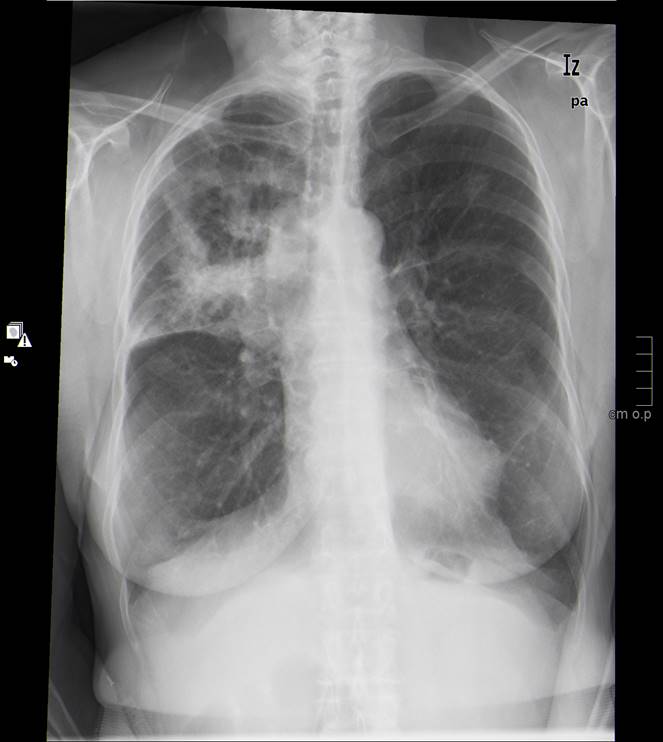

Se realiza rx simple de tórax como primer método diagnóstico ante síndrome respiratorio, dada su rapidez y economía así como su utilidad para descartar muchos procesos ya que da mucha información. Cabe remarcar el papel de la rx simple de tórax, junto con la historia clínica y la exploración, como la prueba básica para el diagnóstico de enfermedades respiratorias.